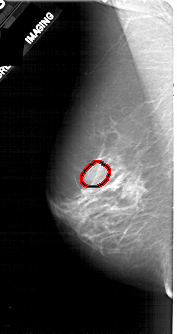

A_1820_1.LEFT_MLO

LEFT_MLO LINES 4996 PIXELS_PER_LINE 2641 BITS_PER_PIXEL 12 RESOLUTION 43.5 OVERLAY

FILE: A_1820_1.LEFT_MLO.OVERLAY

TOTAL_ABNORMALITIES 1

ABNORMALITY 1

LESION_TYPE MASS SHAPE OVAL MARGINS ILL_DEFINED

ASSESSMENT 4

SUBTLETY 4

PATHOLOGY MALIGNANT

TOTAL_OUTLINES 1

BOUNDARY